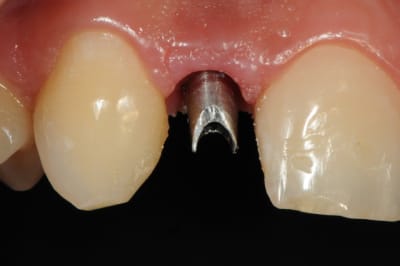

01/09/2010 à 16h28

-cicatrisation de la première vis de cica,

-diamètre plus gros pour la vis de cica

- pilier pour la provisoire

- provisoire moule ION

- ajustage

- polissage soigneux

la suite tout à l'heure, ça sonne à la porte...